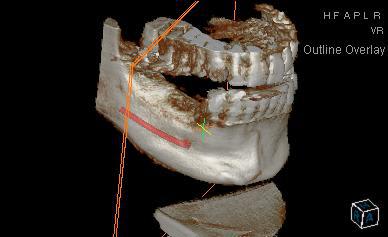

Humator t9r5wy - Eugenol

humator

16/10/2014 à 15h19

voilà un cas avec du metal:couronnes sur les dents bordant l'édentement, et en haut. c'est sur la reconstruction 3d que ça perturbe le plus. Cela dit, tu peux "couper" les artefacts pour les faire disparaitre, si tu souhaites une belle image en volume.

C'est vrai que certaines reconstitutions 3d sont plus moches, quand il y a beaucoup de métal, mais ça ne perturbe pas les coupes.

j'essaye de t'en trouver d'autre bien moches...

ici je n'ai pas "nettoyé" la reconstruction 3d

--

N.Hum

16/10/2014 à 15h26

un autre, où on voit bien les artefacts lié au métal sur la reconstruction, sur les couronnes en bas...

ici c'est un 10x8, ce qui permet de voir assez large